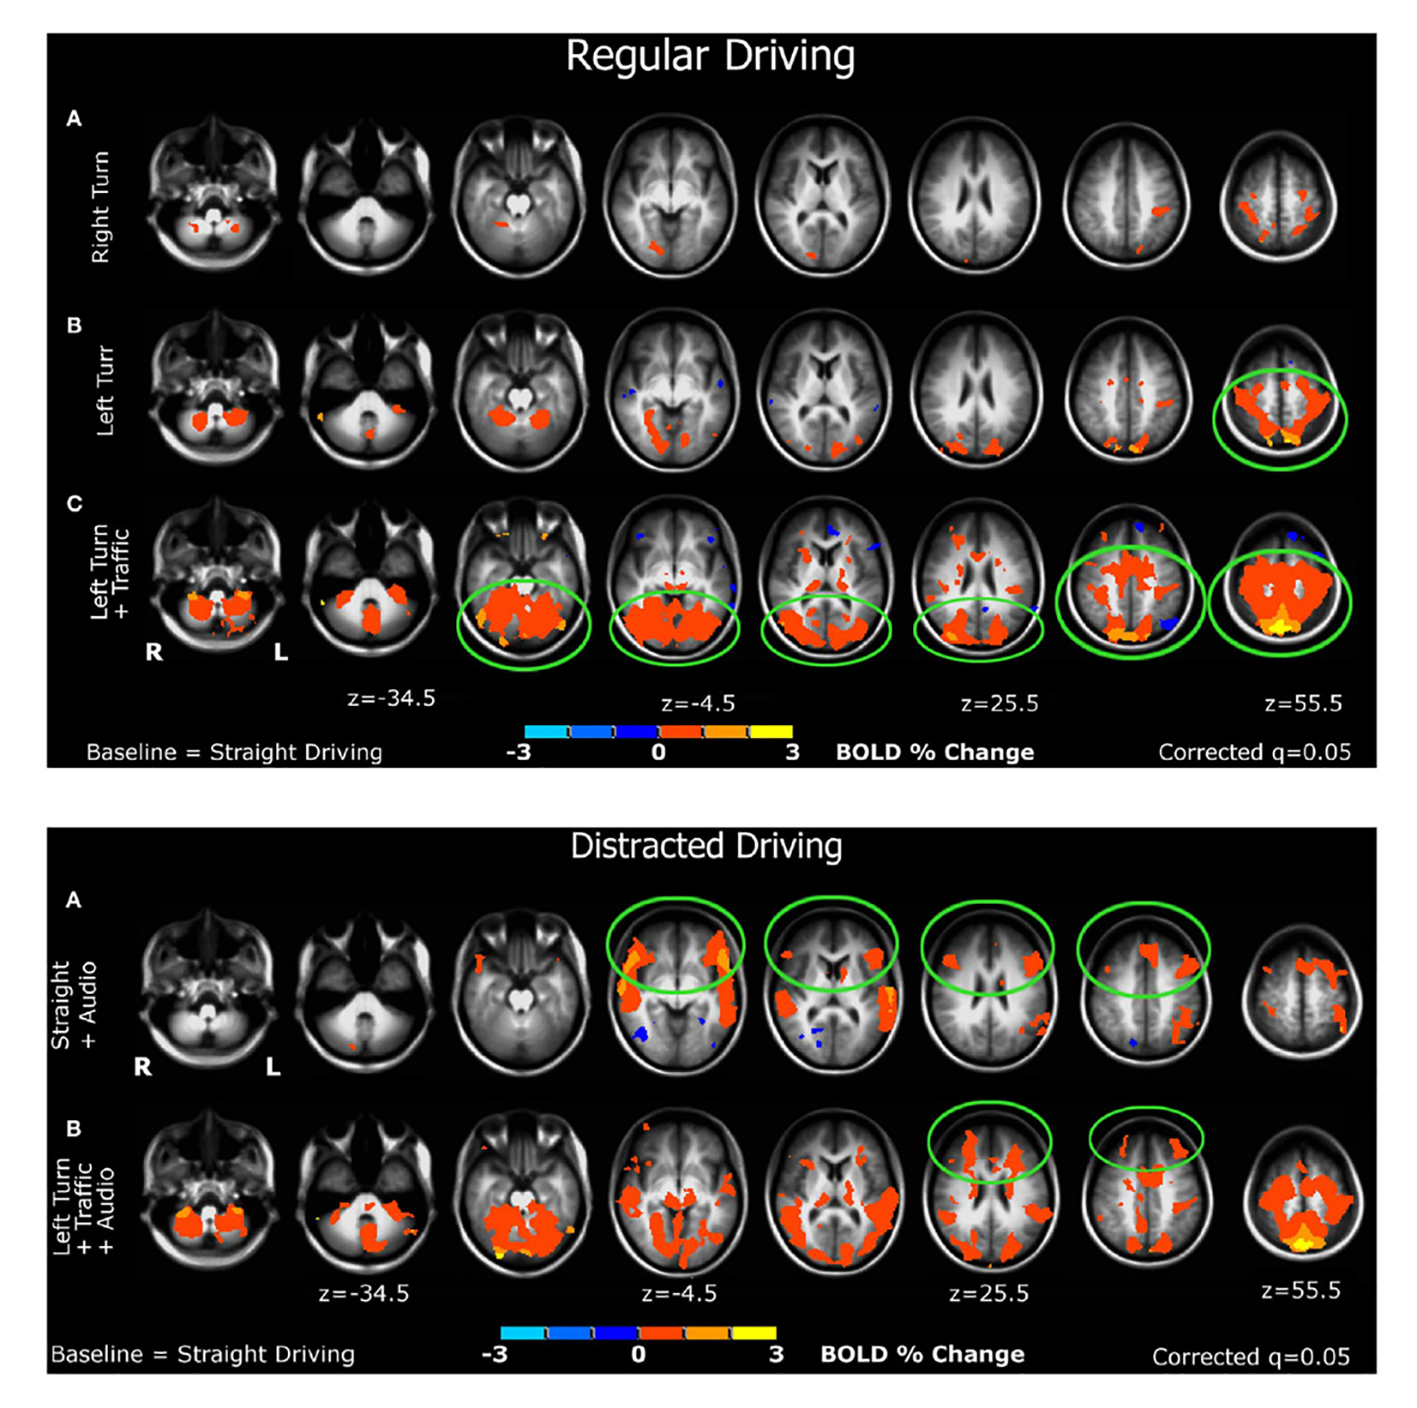

Es generalmente conocido y aceptado que el cerebro tiene una estructura funcional modular, de tal manera que regiones distintas del cerebro se encargan de diferentes tareas (Nicolini y Bifone 2016; Russo, Herrmann y de Arcangelis 2014). Actualmente, la técnica de Imagen por Resonancia Magnética Funcional (FMRI, por sus siglas en inglés) permite ver en tiempo real las diferentes regiones del cerebro que se activan cuando realizamos diferentes tareas. La Figura 8 muestra un ejemplo de este tipo de imágenes, obtenidas de una persona a la que se le puso en un simulador de manejo bajo diferentes condiciones (Schweizer et al. 2013). Se puede ver como se activan regiones distintas dependiendo de si la persona manejaba en línea recta sin distracciones, o cuando tenía que dar una vuelta hacia la derecha o hacia la izquierda con y sin tráfico, con y sin música, etc. Estas regiones miden algunos cuantos centímetros y se activan o desactivan casi instantáneamente cuando la persona cambia de actividad. Hasta aquí todo parece normal y consistente con la estructura modular del cerebro. Sin embargo, cuando consideramos que cada centímetro cúbico de tejido cerebral contiene aproximadamente 60 millones de neuronas (Witelson, Glezer y Kigar 1995; Azevedo et al. 2009), cabe preguntarse con asombro cómo le hacen los cientos de millones de neuronas contenidas en cada una de esas regiones cerebrales, para activarse o desactivarse casi instantáneamente y de forma simultánea ante diferentes estímulos. Cada una de estas regiones es como un árbol de navidad en el que las luces se prenden y apagan de forma sincronizada al recibir diferentes estímulos. La diferencia con el árbol de navidad es que cada una de estas regiones contiene, como ya hemos dicho, cientos de millones de “foquitos”. Claramente, dentro de estas regiones cuyo tamaño va desde 1 cm hasta 15 cm, las neuronas están fuertemente correlacionadas. Aunque 1 cm no parece ser una longitud muy grande para nosotros, desde el punto de vista de una neurona, cuyo tamaño típico es de 2 × 10-3 cm, estas regiones correlacionadas son enormes. Para tener una idea más concreta, si nos hiciéramos del tamaño de una neurona, una distancia de 1 cm equivaldría aproximadamente a 1 Km. Es enorme. Además, la densidad neuronal también es muy grande, pues sería equivalente a tener a todos los habitantes de México (que son como 120 millones) viviendo en una ciudad pequeña como Morelia. ¡Y todas estas neuronas están correlacionadas!

Fuente: Tomada y adaptada de Schweizer et al. (2013).

Figura 8 Imágenes de resonancia magnética funcional que muestran diferentes regiones del cerebro activándose o desactivándose conforme una persona en un simulador de manejo cambia de actividad.